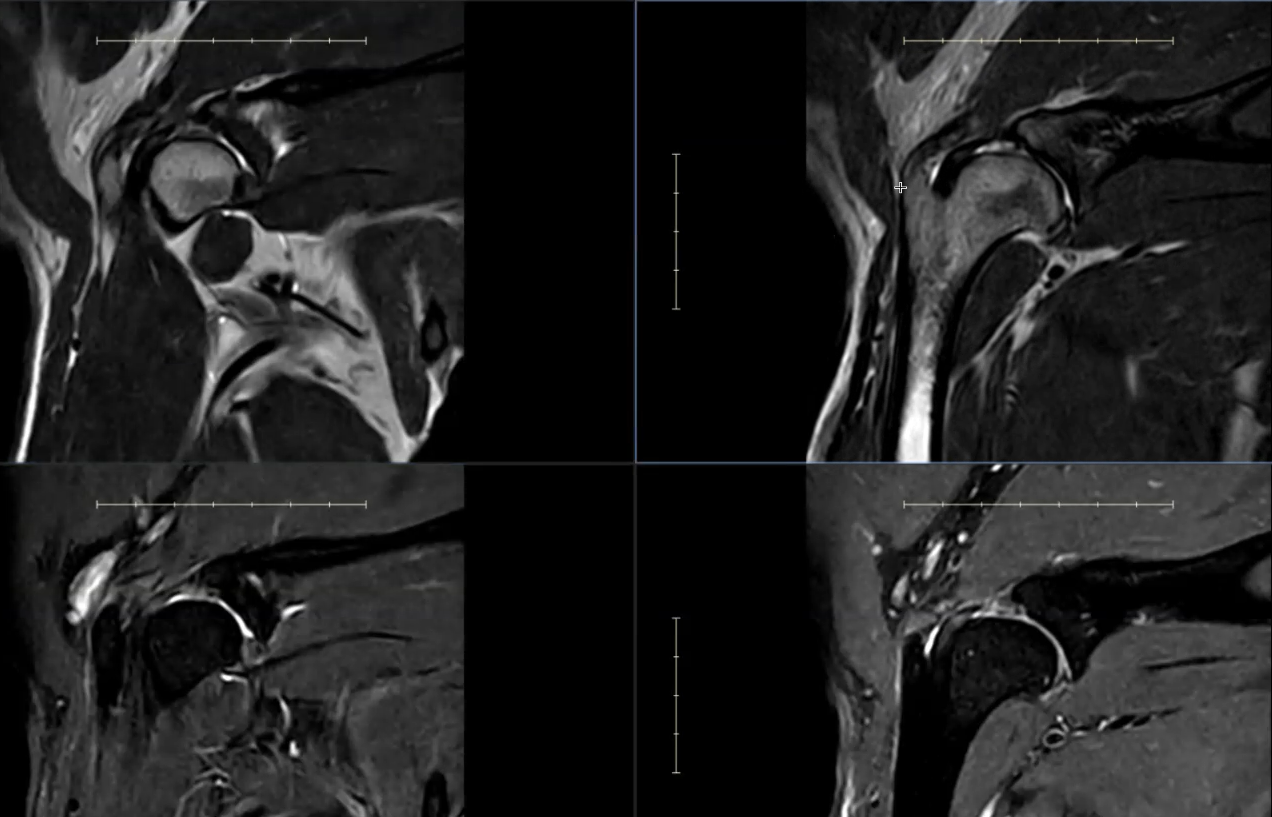

MRI scans of Kal's shoulders showing bilateral pathology. Findings include biceps tendinopathy with fluid in the bicipital tendon sheath (both sides), subscapularis tendon injury, and synovitis, with more advanced changes on the right.

Left Shoulder

Findings in the left shoulder were mild but clinically relevant:

• Subtle enlargement of the supraspinatus tendon at its insertion

• Mild increased signal within the biceps tendon, indicating early inflammation

• Small volume of fluid within the bicipital tendon sheath

These changes are consistent with low-grade tendinopathy and mild inflammation.

Right Shoulder (More Significant Findings)

More pronounced abnormalities were identified in the right shoulder:

• Increased signal and structural changes within the subscapularis tendon, extending into the adjacent muscle

• Contrast enhancement within the joint, consistent with synovitis (joint inflammation)

• Intratendinous signal change in the biceps tendon

• Moderate fluid accumulation within the bicipital tendon sheath

Together, these findings indicate more advanced tendon injury and active joint inflammation.

The MRI findings support bilateral shoulder pathology, with greater severity on the right side.